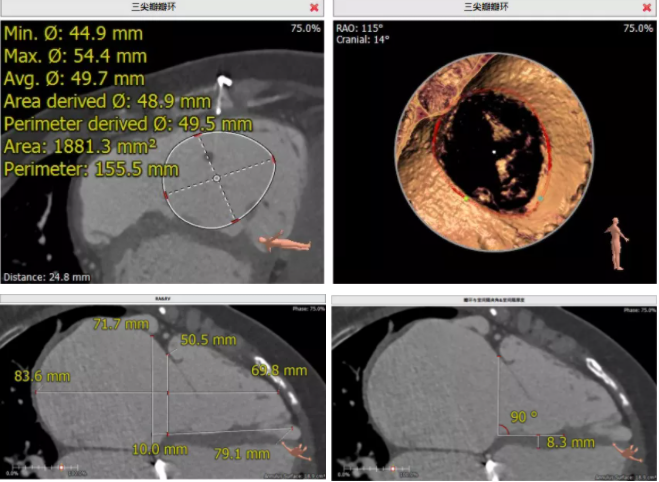

術(shù)前CT評估

患者為68歲女性,14年前因“反復(fù)感冒、氣促”,檢查發(fā)現(xiàn)心臟瓣膜病,接受了“二尖瓣機械瓣置換術(shù)”。約5年前出現(xiàn)雙下肢水腫,活動后心累氣緊,心臟彩超提示:三尖瓣返流。近年來三尖瓣返流逐漸加重并伴有輕微黃疸、雙下肢水腫,雖長期服用利尿劑治療,但效果欠佳。郭惠明教授團隊結(jié)合病史、超聲及CT評估,考慮患者瓣膜置換術(shù)后,三尖瓣重度返流,再次開胸行體外循環(huán)手術(shù)風險高,經(jīng)團隊整體評估,決定采用最適合患者的LuX-Valve三尖瓣置換系統(tǒng)行微創(chuàng)治療,根據(jù)測量結(jié)果選擇植入JS/TTVI-28-55型號的LuX-Valve瓣膜。